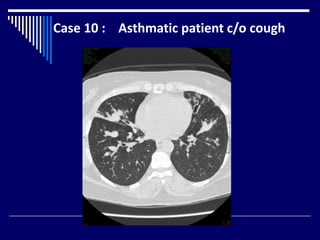

Case 10 : Asthmatic patient c/o cough

Findings

CT chest axial image ( lung window) (1)

Bilateral bronchiectasis (2)

Mucus plugs ( glove finger ) (3)

Dx = ABPA (4)

Case 10 :Asthmatic patient c/o cough

Findings CT chest axialimage ( lung window) (1) Bilateral bronchiectasis (2) Mucus plugs ( glove finger ) (3) Dx = ABPA (4)